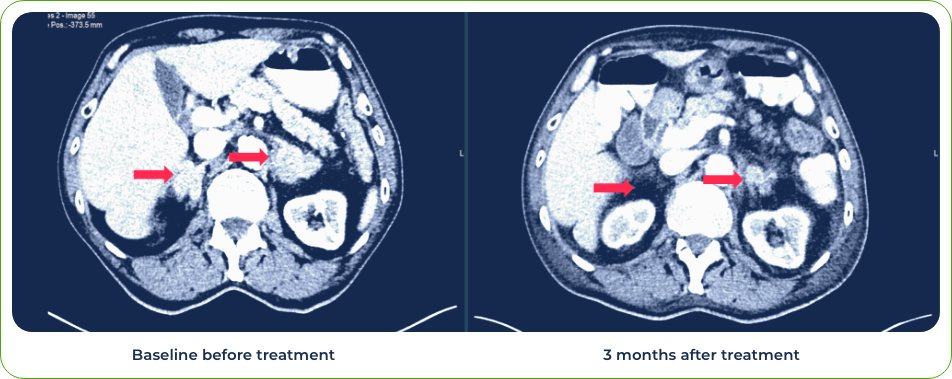

Diagnosis:

Stage IV lung adenosquamous carcinoma

Sites of metastases:

Adrenal glands and brain